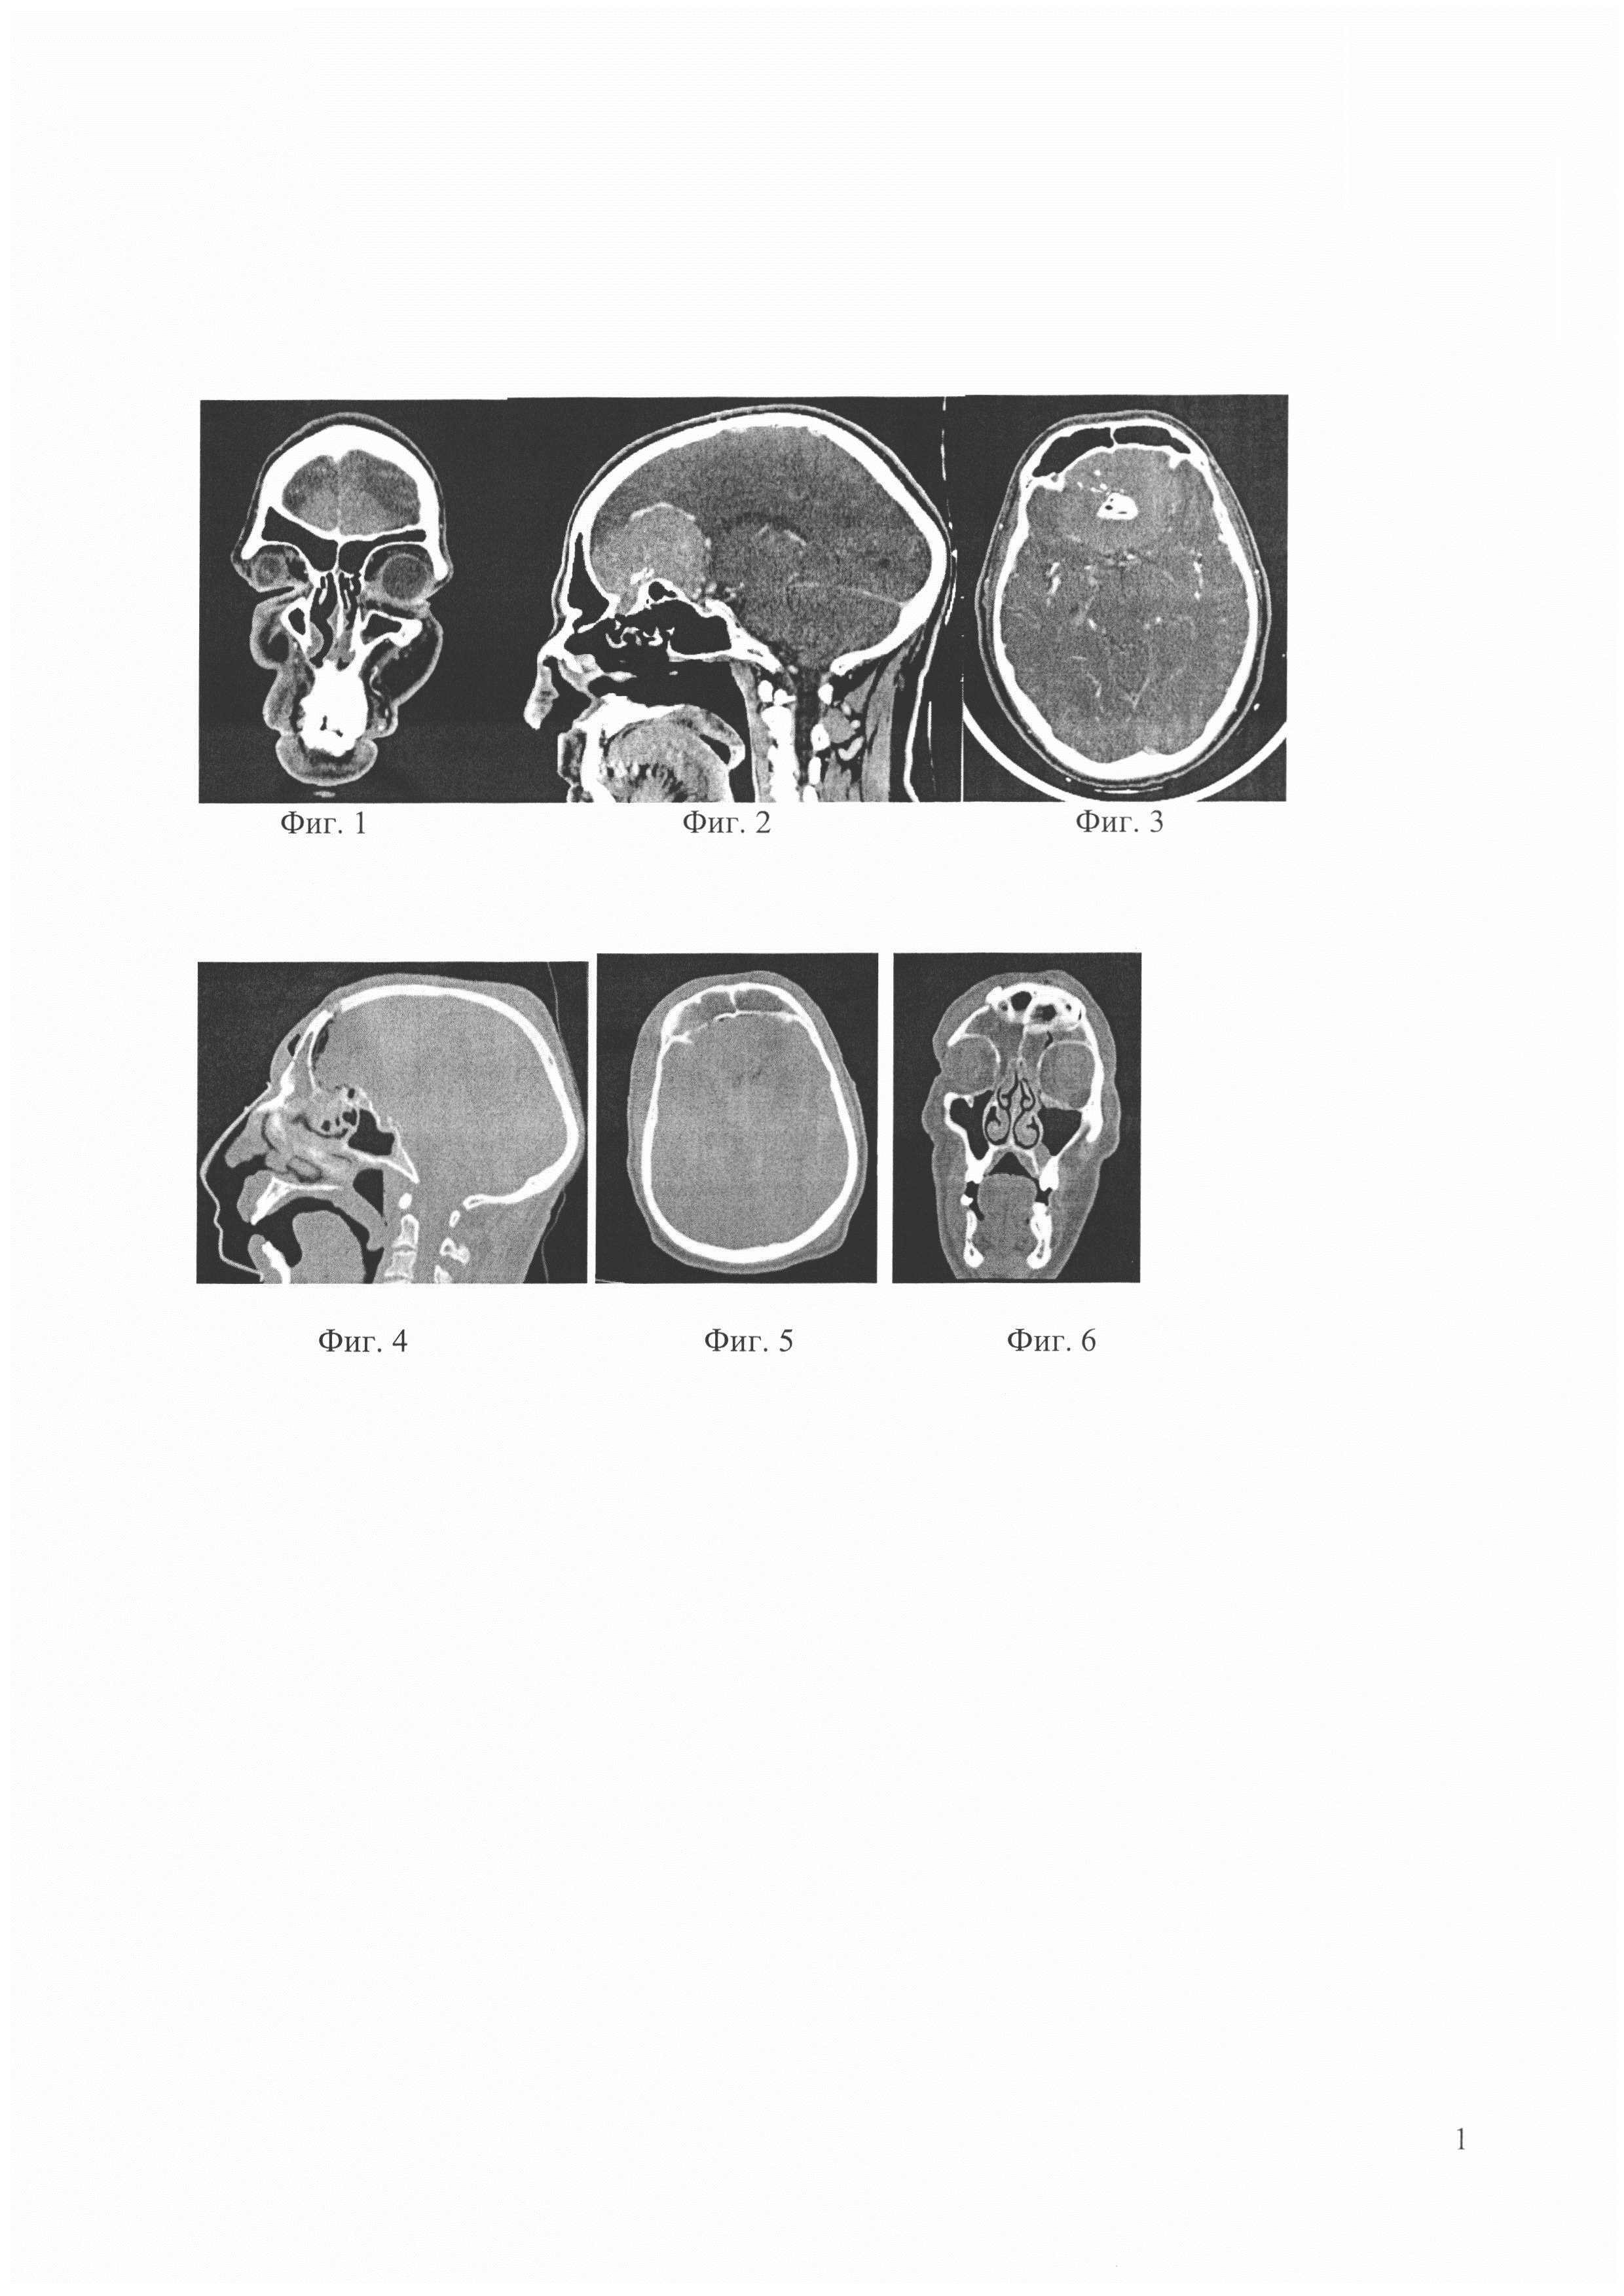

Предлагаемое изобретение поясняется данными компьютерной томографии (КТ) конкретного пациента в до и послеоперационном периодах в трех плоскостях до проведения планового хирургического вмешательства: на фиг. 1 фронтальный срез, фиг. 2 - сагиттальный срез, фиг. 3 - аксиальный срез; 1 сутки после проведенного хирургического вмешательства: на фиг. 4 сагиттальный срез, фиг. 5 - аксиальный срез, фиг. 6 - фронтальный срез.

Принимая во внимание сохраняющиеся жалобы в 2005 г. выполнено КТ исследование головы, на котором было выявлено гиперваскулярное образование в проекции передней черепной ямки. От операции отказался. В течение последующих 10 лет самостоятельно принимал симптоматическую терапию. 12.09.2015 г. был избит неизвестными получил черепно-мозговую травму, в результате чего госпитализирован в стационар, где было выполнено повторное томографическое исследование КТ головы, по данным которого визуализировано экстрацеребральное гиперваскулярное гигантское объемное образование в проекции ольфакторной ямки, перифокальный отек вещества мозга лобных долей, компрессия и деформация переднего колена мозолистого тела, передних рогов боковых желудочков. Консультирован нейрохирургом Новосибирского НИИТО, рекомендовано плановое оперативное лечение, направленное на удаление экстрацеребрального образования (менингиома?). После госпитализации в отделение нейрохирургии проведено КТ головы с контрастным усилением (фигуры 1, 2, 3), по данным которого было подтверждено экстрацеребральное гиперваскулярное внемозговое объемное образование ольфакторной ямки. Размеры образования (вертикальный х ширина х переднезадний) составляли 46 мм х 68 мм х 59 мм.

На следующие сутки после операции выполнен послеоперационный контроль (фигуры 4, 5, 6, 7) в области удаленной опухоли визуализирован гемостатический материал, обе части фронтальной пазухи туго тампонированы жировым аутотрансплантатом, фибрин-тромбинованным клеем и тахокомбом.